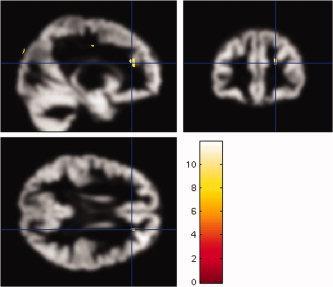

Voxel-based morphometry (VBM) has detected differences between brains of groups of patients with epilepsy and controls, but the sensitivity for detecting subtle pathological changes in single subjects has not been established. The aim of the study was to test the sensitivity of VBM using statistical parametric mapping (SPM5) to detect hippocampal sclerosis (HS) and cortical neuronal loss in individual patients. T1-weighted volumetric 1.5 T MR images from 13 patients with HS and laminar cortical neuronal loss were segmented, normalised and smoothed using SPM5. Both modulated and non-modulated analyses were performed. Comparisons of one control subject against the rest (n = 23) were first performed to ascertain the smoothing level with the lowest number of SPM changes in controls. Each patient was then compared against the whole control group. The lowest number of SPM changes in control subjects was found at a smoothing level of 10 mm full width half maximum for modulated and non-modulated data. In the patient group, no SPM abnormalities were found in the affected temporal lobe or hippocampus at this smoothing level. At lower smoothing levels there were numerous SPM findings in controls and patients. VBM did not detect any abnormalities associated with either laminar cortical neuronal loss or HS. This may be due to normalisation and smoothing of images and low statistical power in areas with larger inter-individual differences. This suggests that the methodology may currently not be suitable to detect particular occult abnormalities possibly associated with seizure onset zone in individual epilepsy patients with unremarkable standard structural MRI.